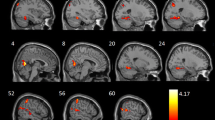

The number of brain regions with reduced GMD was not significantly different between mild COPD patients and the comparison group. Only a few brain regions (including the left middle frontal gyrus and right opercular part/triangular part of the inferior frontal gyrus) had reduced GMD in moderate COPD patients relative to the comparison group (P < 0.05, FWE corrected; Fig. 1 and Additional file 1: Table S2). Brain regions with reduced GMD relative to the comparison group were more extensive in patients with severe COPD than in those with moderate COPD; multiple brain regions demonstrated atrophy in the severe COPD group. The details of these results are shown in Fig. 1 and Additional file 1: Table S2 (P < 0.05, FWE corrected).